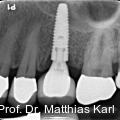

Parallel zur Entwicklung verkürzter Behandlungskonzepte haben sich auch die Außengeometrien zahnärztlicher Implantate hin zu aggressiveren Gewindeformen und konischen Grundkörpern entwickelt. Fotos: © Prof. Dr. Matthias Karl